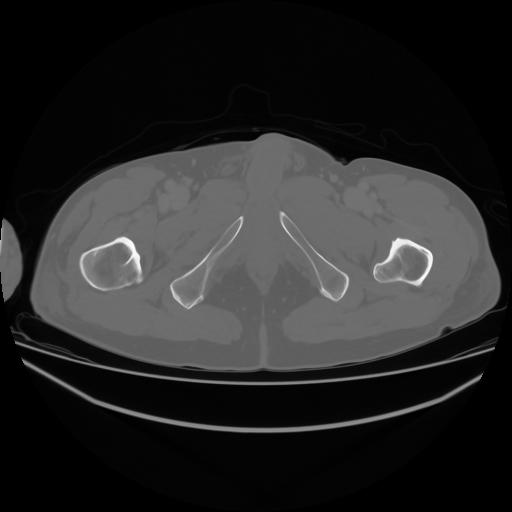

4 CUERPO,CE,Axial,3.0,CUERPO,,